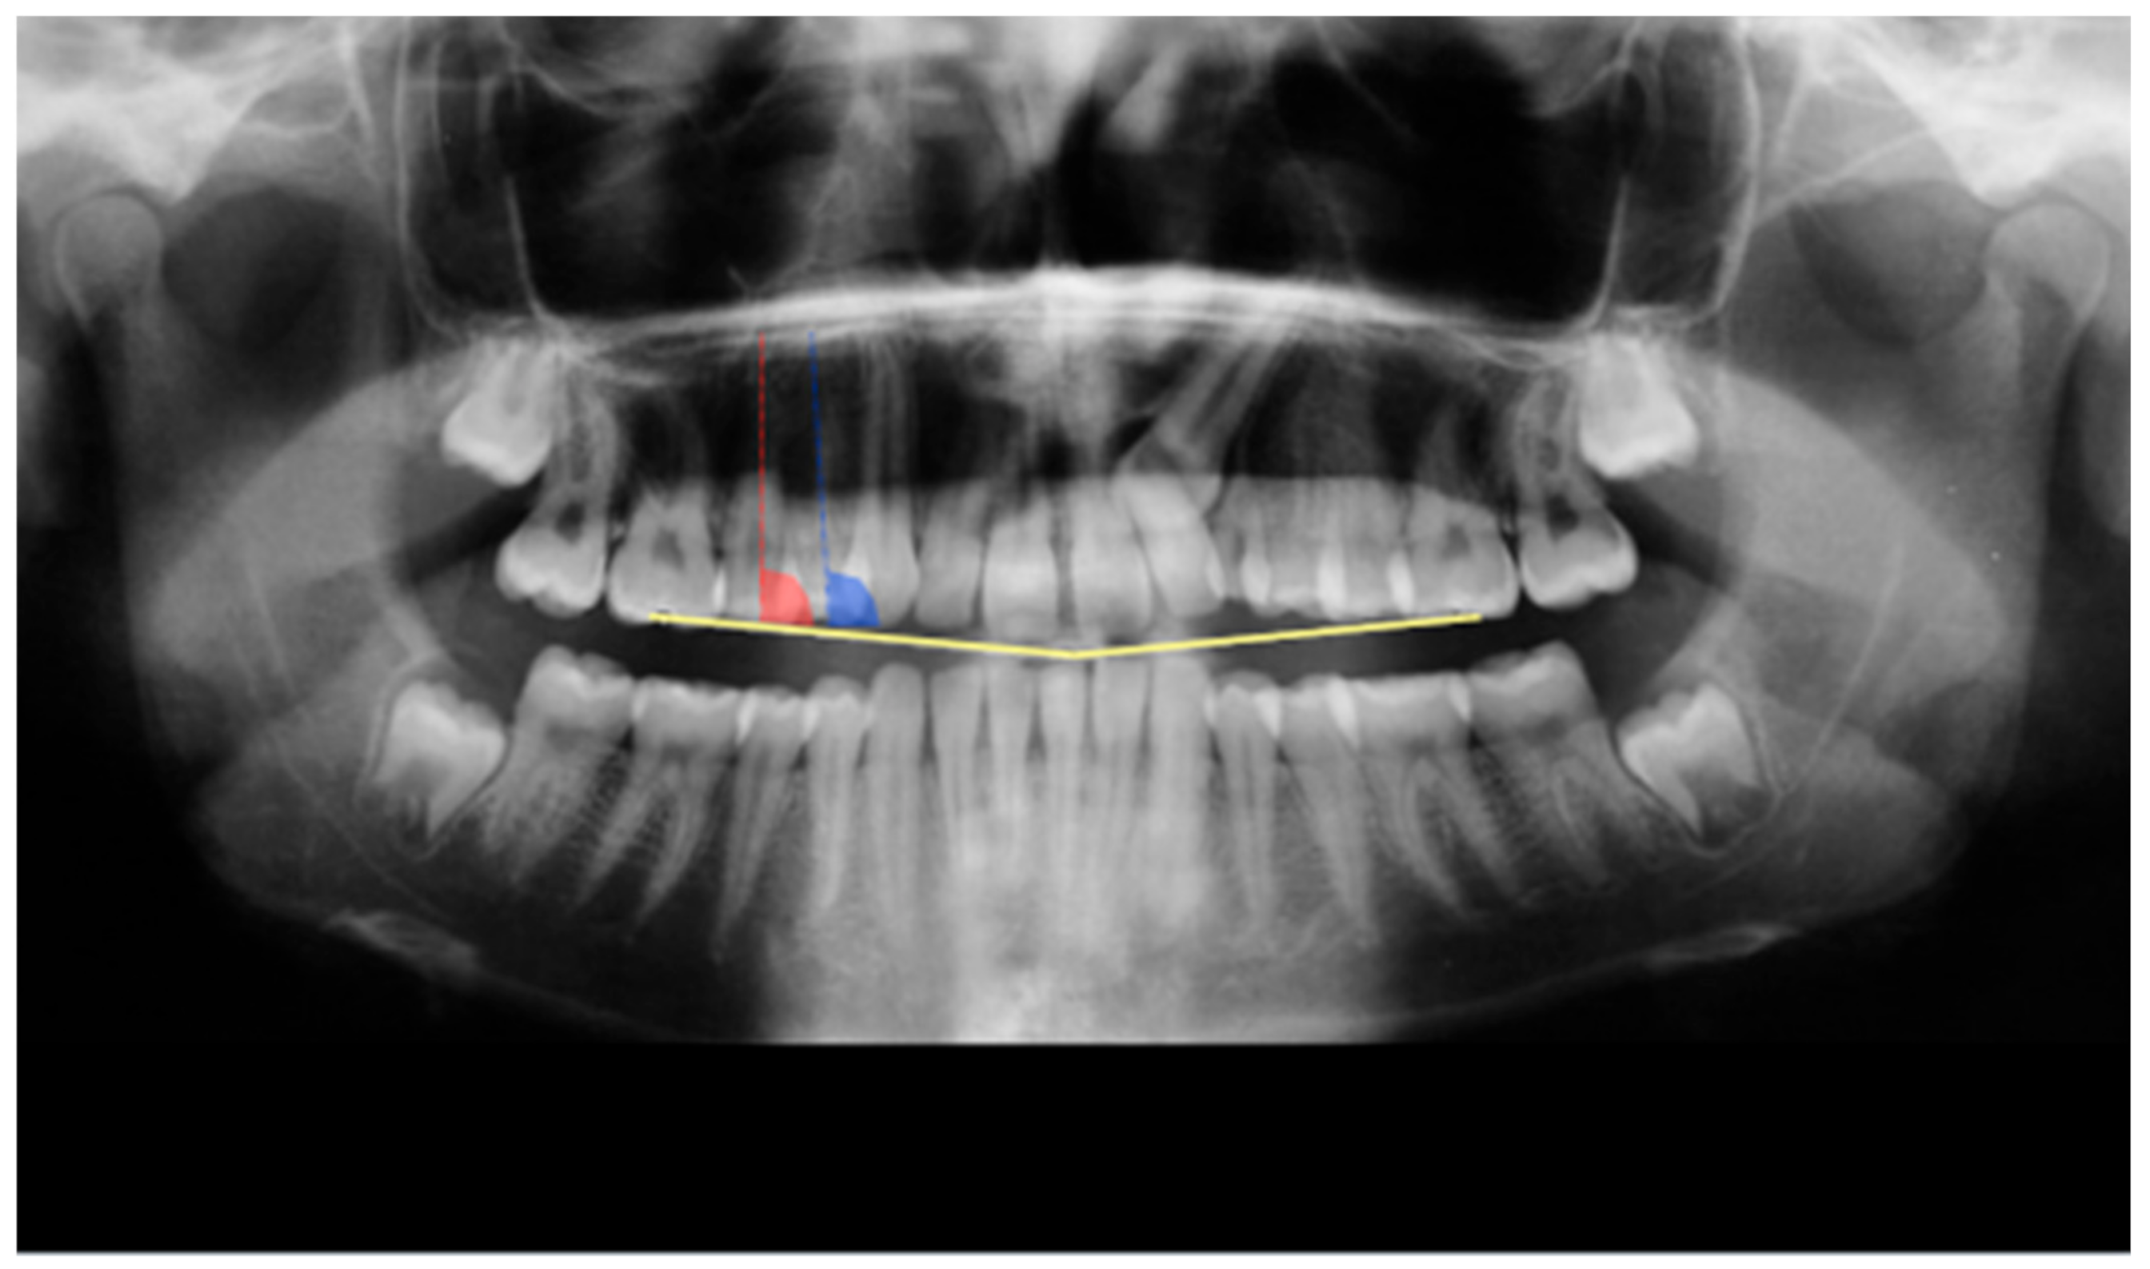

From the initial sample of 45 patients, fifteen patients (mean age 14 ± 0.5 years old; 6 males, 9 females) treated between January 2012 and December 2015 who satisfied inclusion and exclusion criteria were selected. Sample size of at least 9 subjects was necessary to detect a power of 0.8. Sample size was calculated on three subjects on the angular measurements of upper first premolar (difference between means = 1.5 degrees; SD = 1.1 degrees). CBCT acquisition was justified for surgical evaluation of impacted canine, observed at first with panoramic radiography. All of the following measurement procedures on panoramic radiography and CBCT were performed by a single operator. Calibration was performed by two different expert operators to the person who performed the measurements in two different times and double blinded. Then, the main operator, once calibrated, performed the measurements twice with a time interval of one month for all the patients. Therefore, the mean error and 95% confidence intervals (CIs) between the repeated recordings were calculated using the Methods of Moments estimator (MME) variance estimator. The measurement error for angular measurements was 0.9 degrees (range 0.5 and 1.2 degrees). An occlusal plane (PO) was defined on panoramic radiography as a line passing through upper first molar cuspids and upper mesial incisal edge point. Moreover, a dental axis (Axis) was defined as a line from cuspids to apex of upper premolars. The mesiodistal angulation of upper first (U4) and second (U5) premolars was identified by measuring the mesial angle between PO and Axis using ImageJ Software (freeware) on panoramic radiography for left and right sides (Figure 1).

Figure 1.

Measurement of mesiodistal angulation on panoramic radiography. The mesiodistal angulation of U4 and U5 was identified by the mesial angle between PO and Axis.